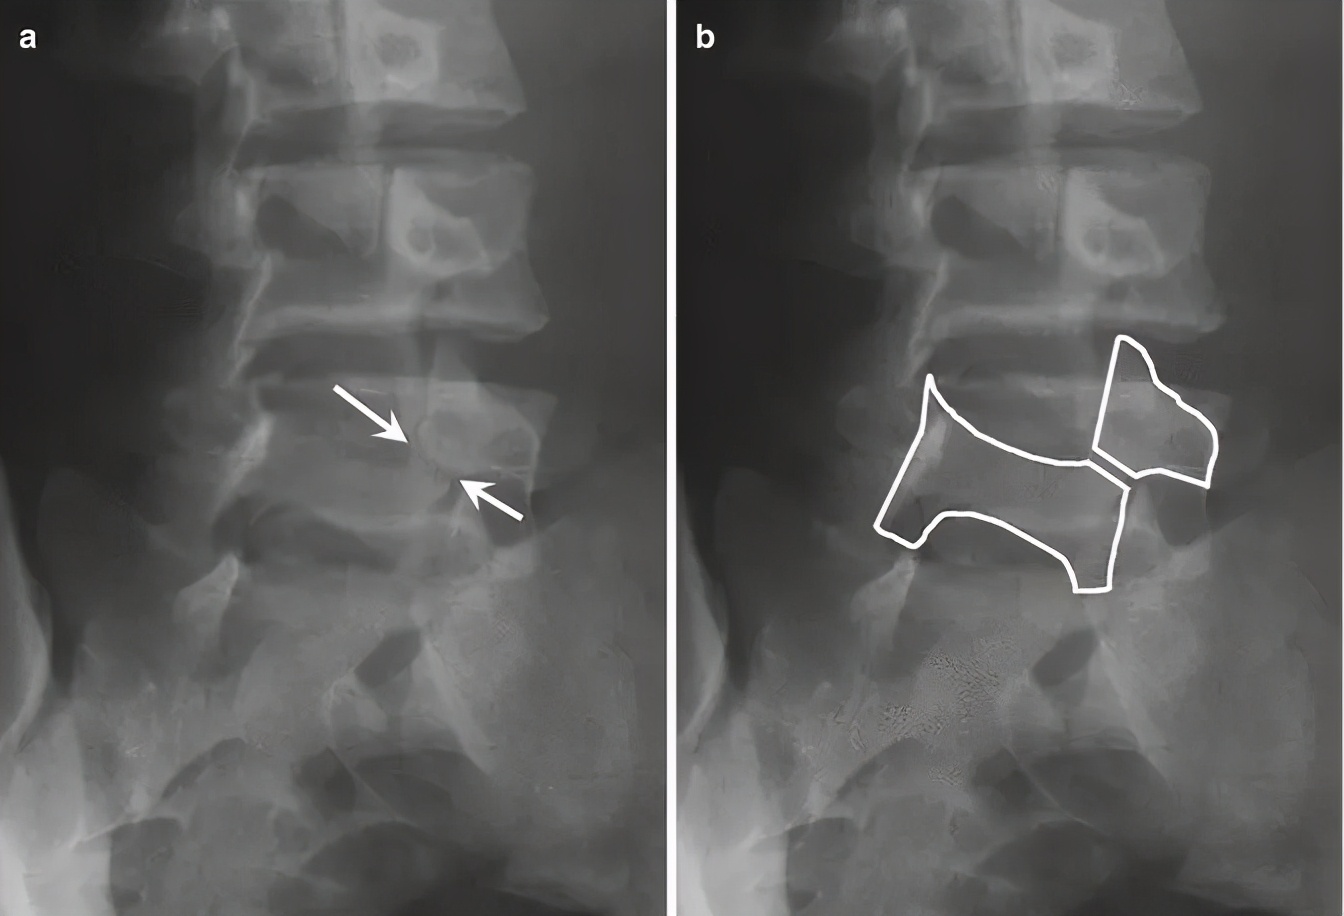

腰椎双斜位片是需要的,通常表现为“ 苏格兰狗脖子”断了(见下图) 。但对于一些隐匿的患者,腰椎双斜位片是看不出的,这时候需要行腰椎CT、MRI进一步明确诊断,少数部分需行核素骨扫描才能明确诊断。

图:箭头所指为苏格兰狗脖子断了

腰椎斜位片上苏格兰狗脖子=腰椎峡部

图:腰椎斜位片,图中黑色箭头所示为峡部裂